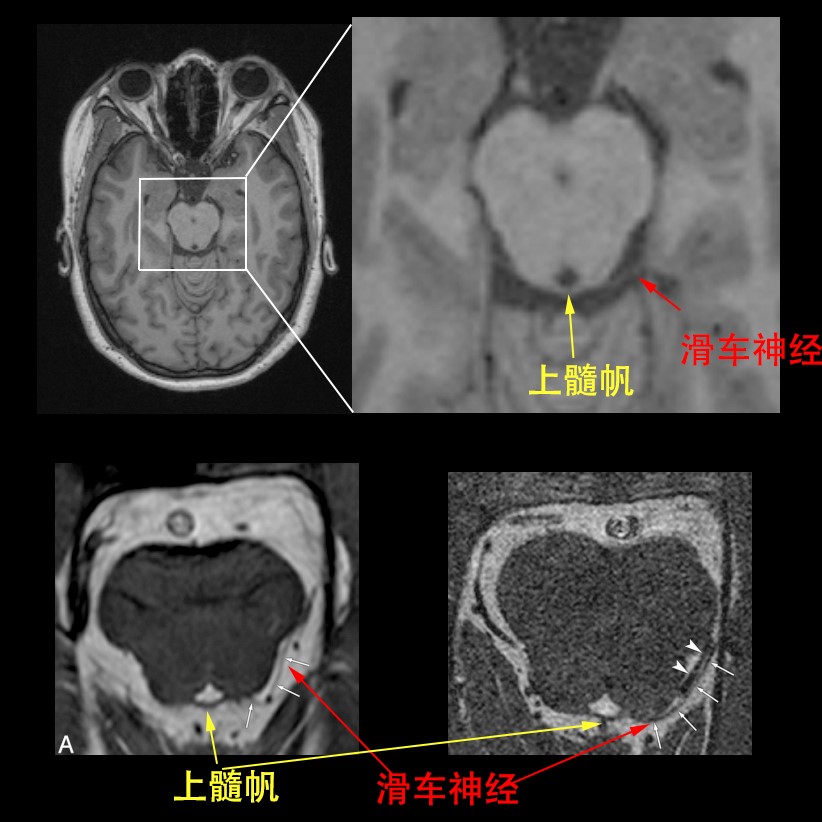

滑车神经

【图】滑车神经属于哪个神经 教你识别外展神经损伤的鉴别诊断

神经解剖外传——简单又不简单的滑车神经

让你过目不忘非常容易误诊小结构滑车钙化

神经解剖外传——简单又不简单的滑车神经

《系统解剖学》课件 Ⅳ,滑车神经 纤维成分:躯体运动纤维 行径:中